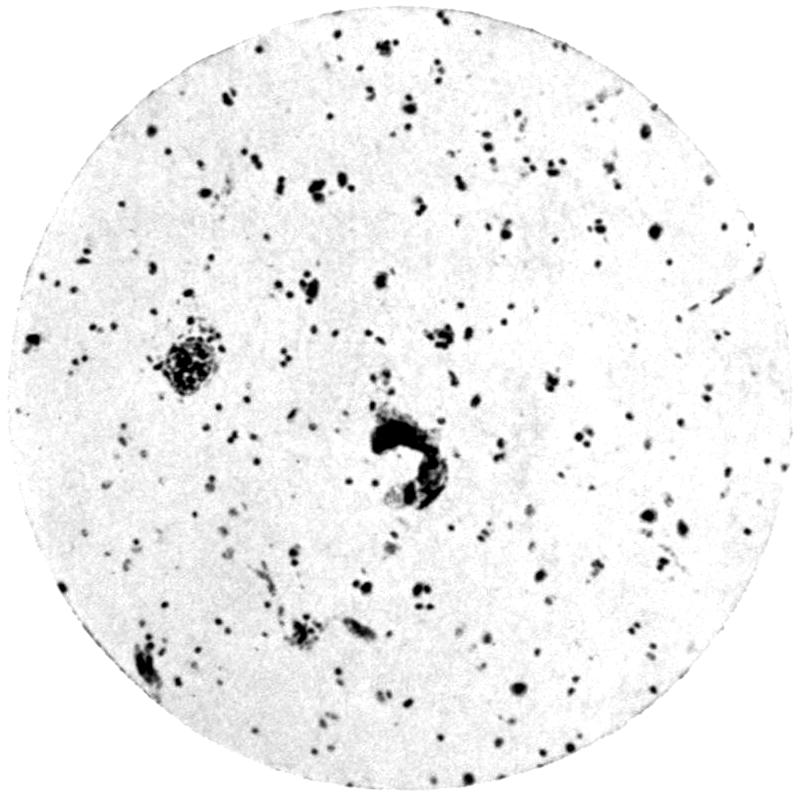

LIST OF PLATES

FACING

PAGE

Plate I. 92